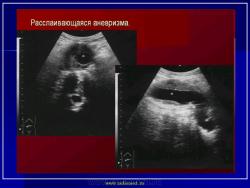

УЗИ  аорты.